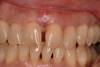

The pretreatment situation.

Figure 13